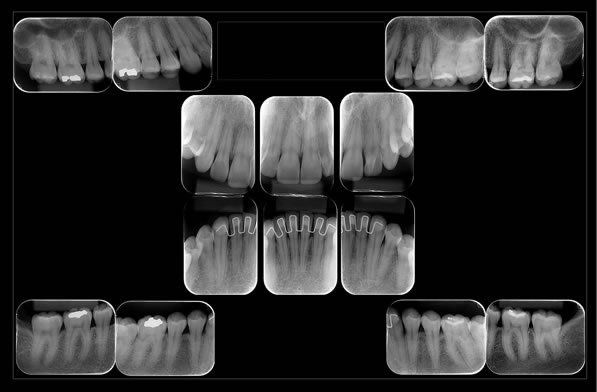

Periapical